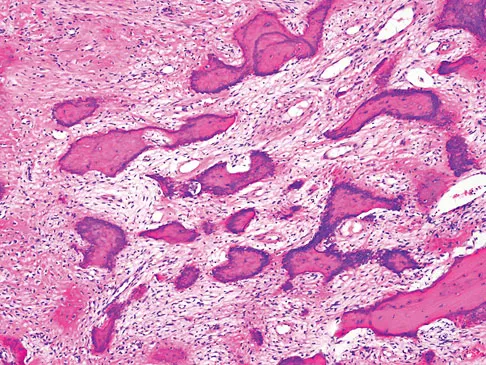

Figures 61a and 61b show the CT and MRI scans of a 40-year-old man who has hip pain. He undergoes total hip arthroplasty and curettage and cementation of the lesion as shown in Figure 61c. Histopathologic photomicrographs of the curettage specimen are shown in Figures 61d and 61e. What is the best course of treatment?

Explanation

The definitive surgery would be removal of the entire resection bed, and in this case of dedifferentiated chondrosarcoma, a hemipelvectomy was performed. The MRI and CT scans show an aggressive cartilage lesion. The histology, representative of a dedifferentiated chondrosarcoma, shows a bimorphic low-grade cartilage lesion with high-grade spindle cell sarcoma. The cartilage lesion is usually an enchondroma or low-grade chondrosarcoma. The dedifferentiated portion is typically a malignant fibrous histocytoma, osteosarcoma, or fibrosarcoma. Weber KL, Pring ME, Sim FH: Treatment and outcome of recurrent pelvic chondrosarcoma. Clin Orthop Relat Res 2002;397:19-28.